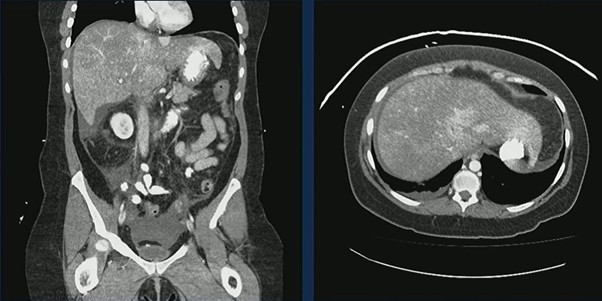

Case in Point: A 44-year-old woman with prior cerebrovascular accidents and paroxysmal nocturnal hemoglobinuria presented with abdominal pain, nausea, and vomiting. CT demonstrated an enlarged, heterogeneous liver with markedly heterogeneous enhancement and small-volume ascites—classic features of hepatic venous outflow obstruction.

Ultrasound confirmed hepatic vein occlusion.